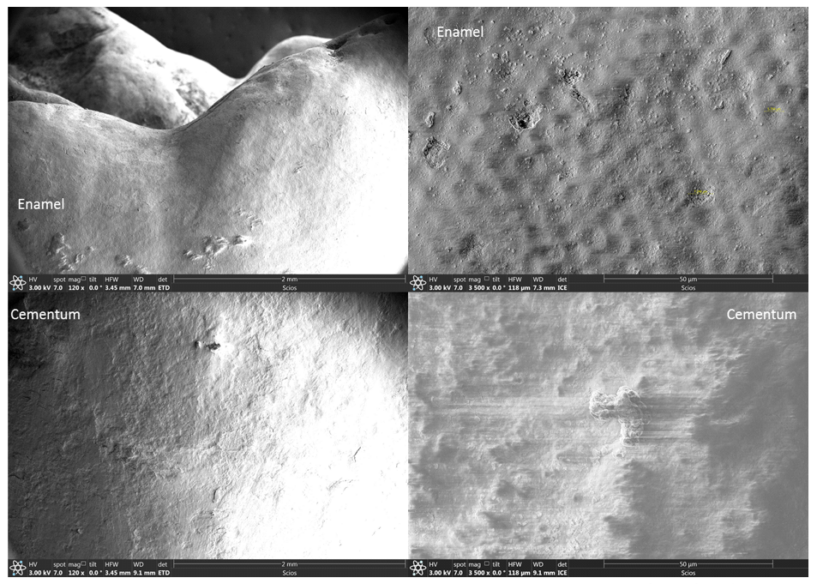

Vanjska strana ljudskog zuba sastoji se od dva dijela: krunice prekrivene caklinom (Slika 1.) i korijena prekrivenog cementom (slika 2.). Površina emajla je glatkija od cementa. Mikrostanične strukture promjera 5~7 µm mogu se uočiti na caklini, kako u OM (slika 1.) i u SEM (slika 3).

Slika 3. Caklina i cement, pod sekundarnom elektronskom mikroskopijom (SEM) prije eksperimenta.

Nakon 2 mjeseca potapanja ljudskog zuba u zubnu pastu Rising® Denta 5000 Plus s fluorom, ljudski zub je opran i ponovno karakteriziran s OM i SEM kako bi se istražile sve promjene na površini zuba. Snimljene slike navedene su na slikama 4 do 6 u nastavku. Primijetite da su uočene mikro-pukotine na površinama emajla i cementa. Površina cakline počela je pokazivati male skupine mikro-pukotina s duljinama istezanja od 50 µm do 100 µm (slika 5.); dok su se na površini Cementuma pojavile opsežne mreže mikro-pukotina (slika 6.). Očito je da je gustoća mikro-pukotina na površini cementa puno veća nego na površini cakline.

Slika 5. Caklina pod sekundarnom elektronskom mikroskopijom (SEM) nakon 2 mjeseca eksperimenta; Caklina je počela pokazivati male skupine pukotina.

Slika 6. Cement pod sekundarnom elektronskom mikroskopijom (SEM) nakon 2 mjeseca eksperimenta; Opsežne mreže mikro-pukotina pokazale su se na površini cementa.